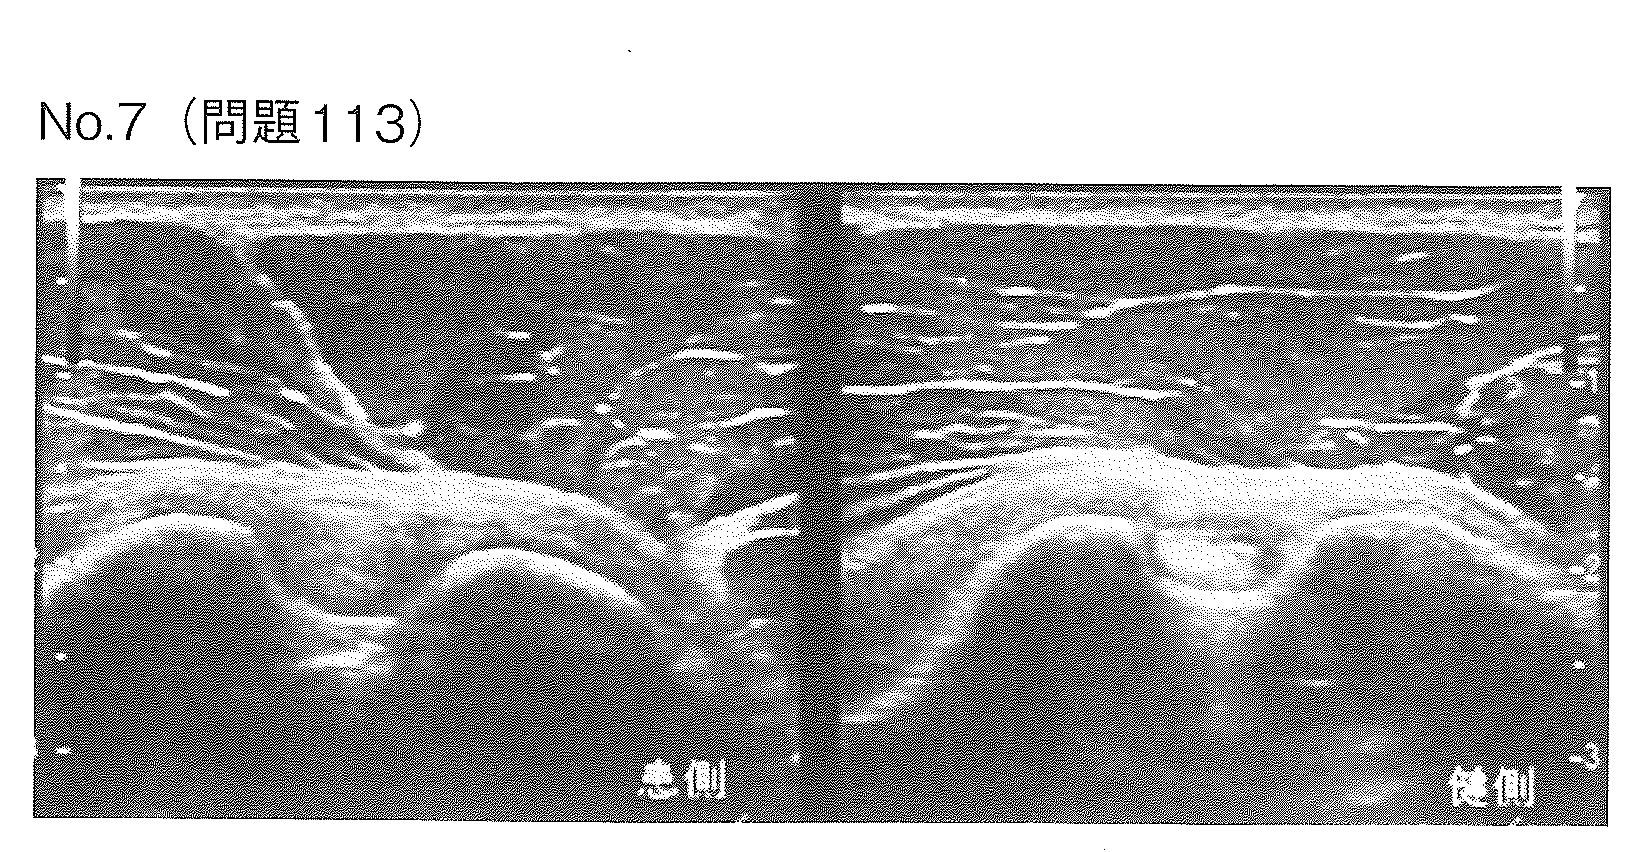

20歳男性。体操部に所属している。つり輪の練習中に左肩部に痛みを自覚した。肩関節の挙上は違和感はあるが可能である。肩前方の短軸超音波画像で(別冊No.7)を別に示す。考えられるのはどれか。

1→腱周囲の液貯留(腱鞘炎)の所見です。 超音波画像(結節間溝レベルの短軸像)で、上腕二頭筋長頭腱の周囲に液体貯留(低エコー像)や腱の腫大が見られる場合、長頭腱炎と診断されます。

2→2, 3, 4:これらは関節唇や骨の損傷であり、結節間溝のエコー像とは異なります。